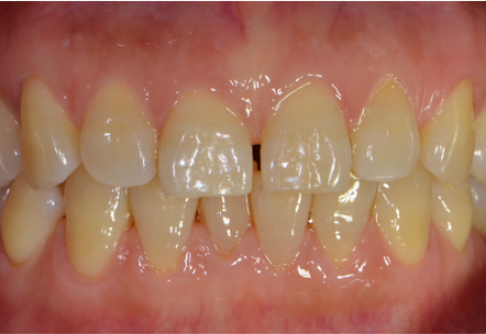

Before

After

위 치료 사례는 굿프렌즈치과에서 직접 치료를 받은 환자 분의 사례로 직접 동의를 얻어 게재되었습니다.